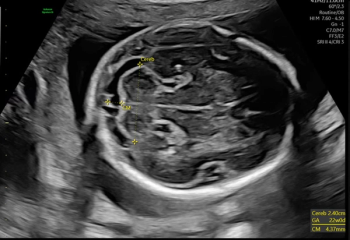

External validation testing revealed a deep learning combination of breast MRI, ultrasound and clinical factors had a 10 percent higher AUC for predicting axillary lymph node metastasis than sole use of MRI- or ultrasound-based deep learning models in patients with breast cancer.